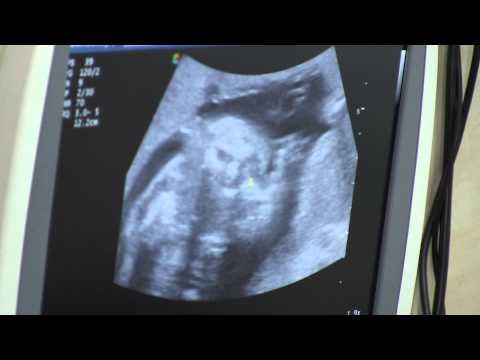

Абонирайте се за канала ни! Очаквайте нов епизод всяка сряда! В новия епизод Меги ще ви разкаже от своя личен опит изследванията, през които трябва да мине всяка бременна. Кои са тези изследвания, които ви се полагат по здравна каса и кои са едни от най-важните изследвания за вашето бебче вижте в новия епизод.